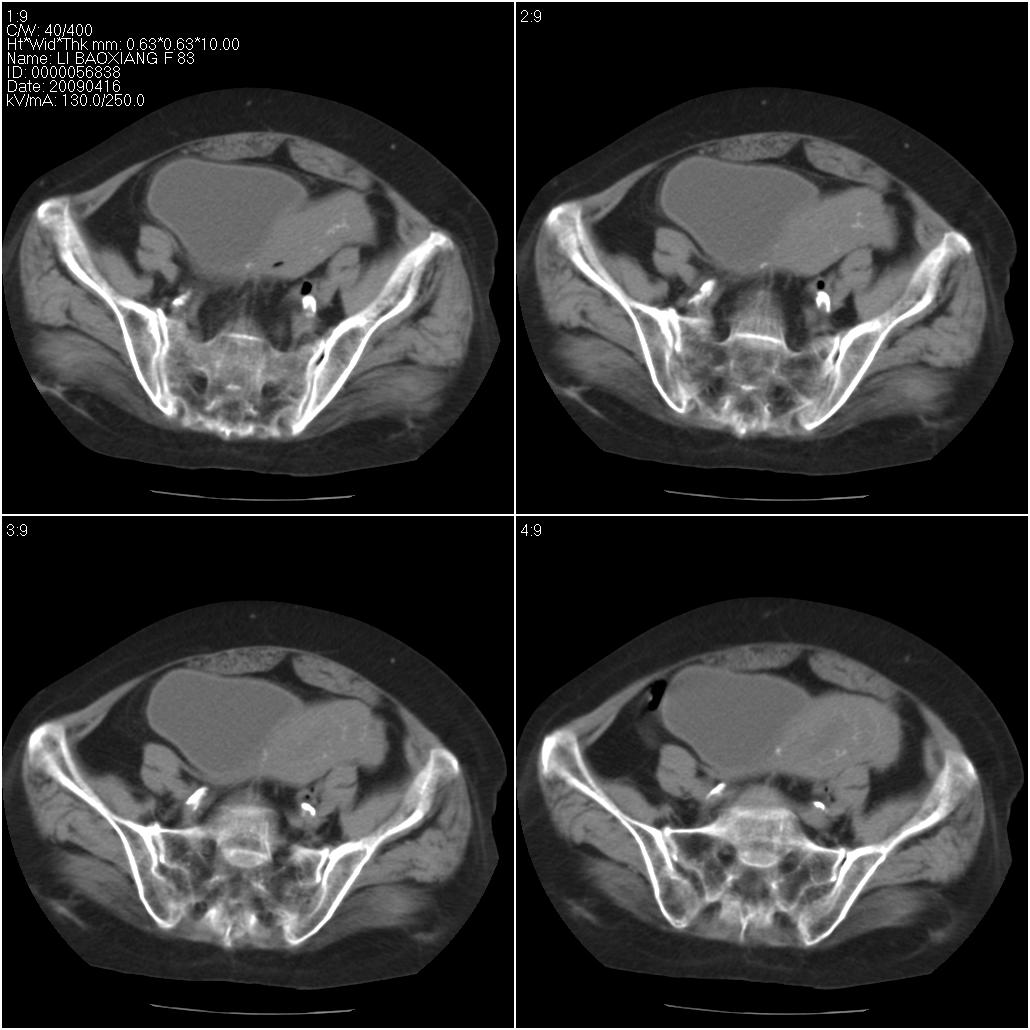

标题: CT19496:女性,83岁。阴道出血多年,患者一般情况良好。 [打印本页]

标题: CT19496:女性,83岁。阴道出血多年,患者一般情况良好。

乙状结肠病变累及子宫,建议结合妇科检查

考虑乙状结肠肿瘤累及子宫;建议行肠镜检查。

考虑:乙状结肠癌累及子宫,建议钡剂灌肠。

乙状结肠癌累及子宫

乙状结肠癌侵犯子宫可能性大。